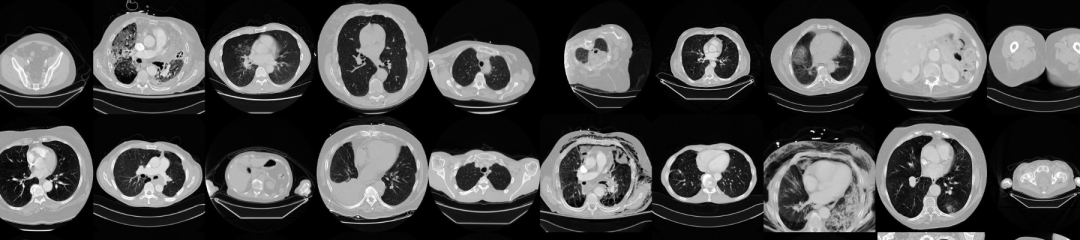

CT 医学图像

下载链接:http://ew0bt.avtk.cn/a6

该数据集旨在允许测试不同的方法来检查与使用对比度和患者年龄相关的 CT 图像数据的趋势。基本思想是识别与这些特征密切相关的图像纹理、统计模式和特征,并可能构建简单的工具,在这些图像被错误分类时自动对其进行分类(或查找可能是可疑情况、错误测量或校准不良机器的异常值)